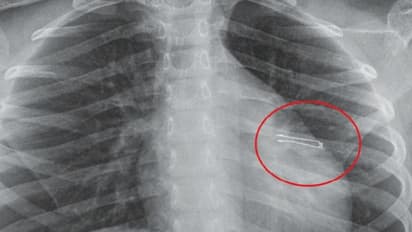

ആലുവ: ഏഴുവയസ്സുകാരിയുടെ ശ്വാസകോശത്തില് കുടുങ്ങിയ എല്ഇഡി ബള്ബ് ശസ്ത്രക്രിയ ചെയ്യാതെ പുറത്തെടുത്തു. കണ്ണൂര് സ്വദേശിനിയായ കുട്ടിയുടെ ശ്വാസകോശത്തില് നിന്നാണ് ബള്ബ് പുറത്തെടുത്തത്.

രാജഗിരി ആശുപത്രിയില് ‘റിജിഡ് ബ്രോങ്കോസ്പി’ എന്ന സങ്കീർണ നടപടിയിലൂടെയാണ് ബള്ബ് പുറത്തെടുത്തത്. കൂര്ത്ത അഗ്രമുള്ള ബൾബ് പുറത്തെടുക്കുന്നതിനിടെ ശ്വാസകോശത്തിൽ മുറിവോ രക്തസ്രാവമോ ഉണ്ടായില്ലെന്ന് പീഡിയാട്രിക് സർജറി വിഭാഗത്തിലെ ഡോ. അഹമ്മദ് കബീർ പറഞ്ഞു.

ബള്ബ് കുടുങ്ങിയതിനെ തുടര്ന്ന് അസ്വസ്ഥതകള് അനുഭവപ്പെട്ട കുട്ടിയെ ആദ്യം കോഴിക്കോടുള്ള സ്വകാര്യ ആശുപത്രിയില് എത്തിക്കുകയായിരുന്നു. ബൾബ് പുറത്തെടുക്കാനുള്ള സാങ്കേതിക വിദ്യ ലഭ്യമാണെന്നതിനാൽ വെള്ളിയാഴ്ച അർധരാത്രിയോടെ രാജഗിരിയിൽ എത്തിക്കുകയായിരുന്നു. കൂര്ത്ത അഗ്രം പുറത്തേക്ക് തിരിഞ്ഞ നിലയിലാണ് ബള്ബ് ശ്വാസകോശത്തില് കുടുങ്ങിക്കിടന്നിരുന്നത്. രണ്ടുമണിക്കൂര് നീണ്ടുനിന്ന പരിശ്രമത്തിനൊടുവിലാണ് ബള്ബ് പുറത്തെടുത്തത്.